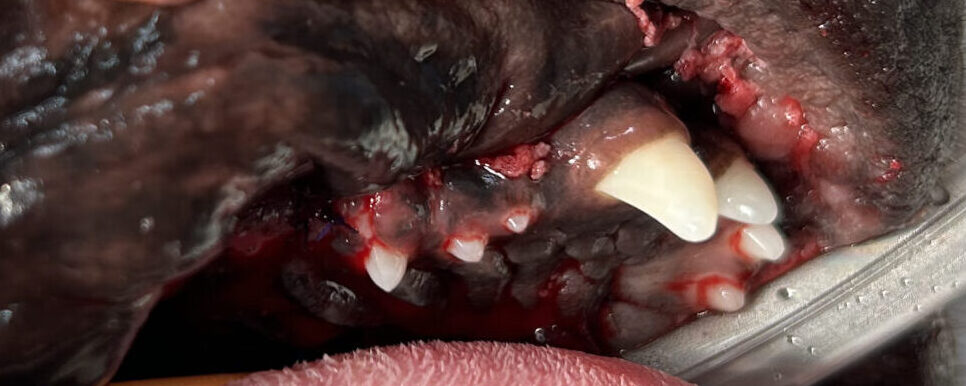

以下の写真は歯冠破折で来られたわんちゃんの写真です。

画面一番左側の歯が折れており、歯髄が露出しています。